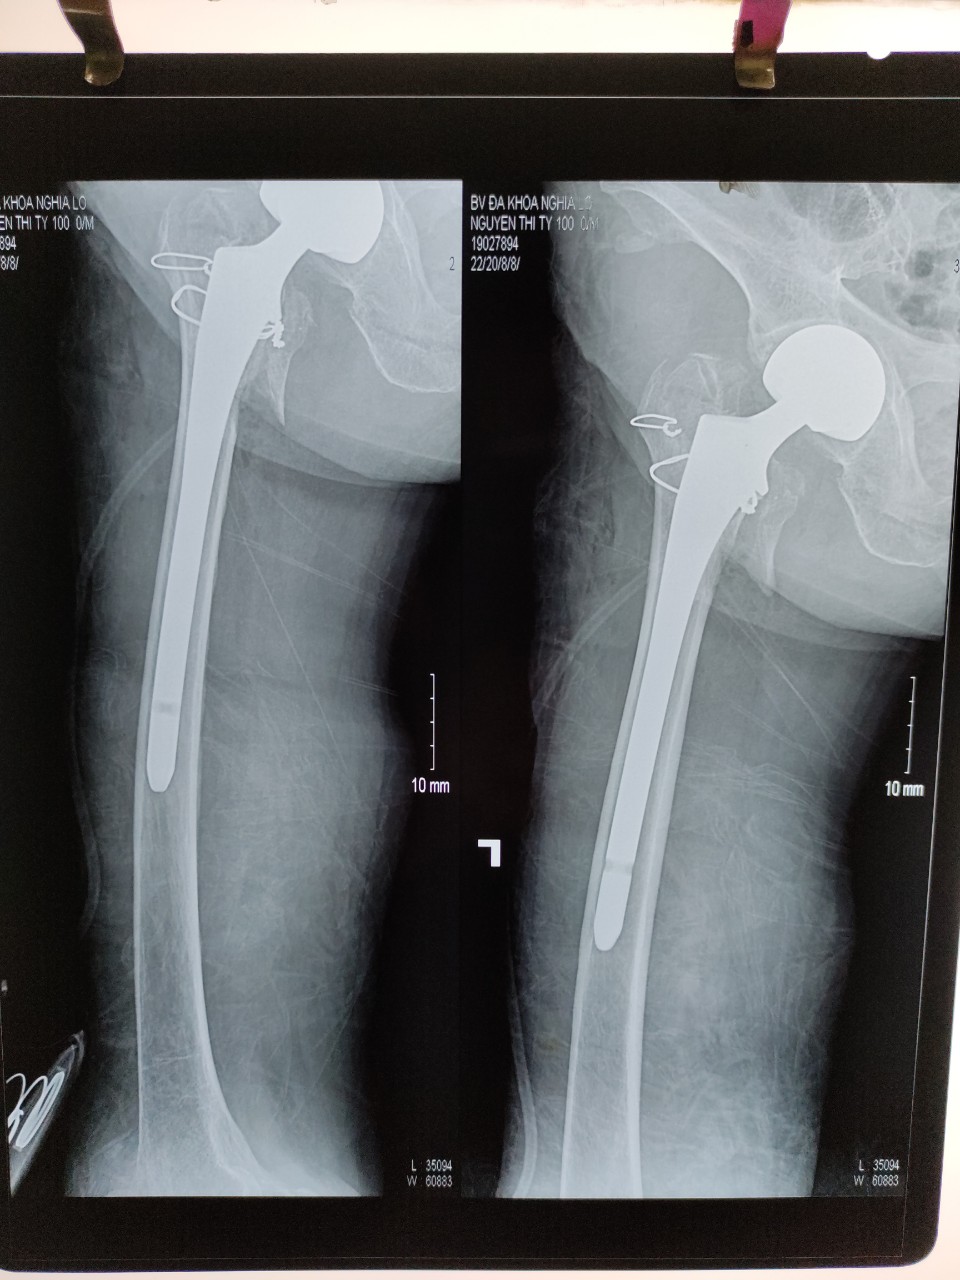

Vừa qua, khoa Chấn thương chỉnh hình - Bệnh viện ĐKKV Nghĩa Lộ đã tiến hành ca Phẫu thuật thay khớp háng bán phần cho bệnh nhân N.T.T 100 tuổi (địa chỉ TTNT Trần Phú, huyện Văn Chấn). Bệnh nhân nhập